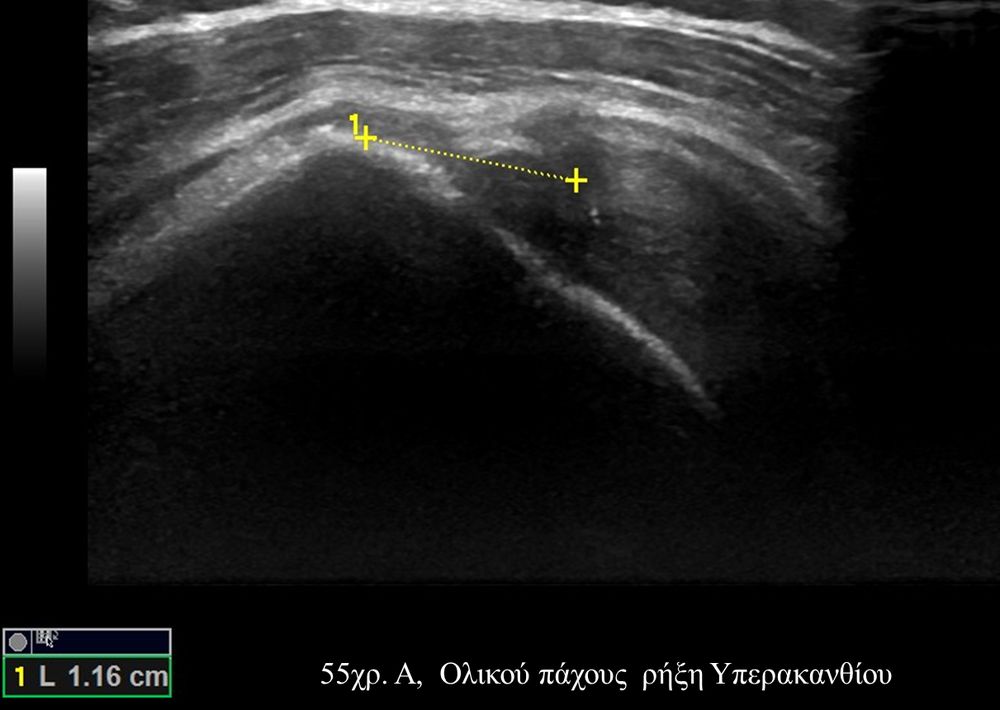

Είναι μια νέα μέθοδος που χρησιμοποιεί υψηλής ευκρίνειας υπερήχους για τη διάγνωση μυοσκελετικών παθήσεων που αφορούν τένοντες, μυς, συνδέσμους, νεύρα και περιφερικές αρθρώσεις. Η μέθοδος αναπτύχθηκε τα τελευταία χρόνια και αποτελεί αναπόσπαστο μέρος στη διαφορική διάγνωση παθήσεων που αφορούν τηνορθοπαιδική, αθλητιατρική, ρευματολογία και παιδιατρική.

Πρόκειται για υπερηχογράφημα υψηλής ευκρίνειας που επιτρέπει την λεπτομερέστατη απεικόνιση (σε επίπεδο χιλιοστού) ακόμη και πολύ μικρών/επιφανειακών ανατομικών δομών και απαιτεί ειδικό υπερηχογραφικό εξοπλισμό καθώς και εξειδίκευση του ακτινολόγου. Η εξέταση γίνεται με δυναμικό τρόπο, δηλ εκτελούνται δοκιμασίες κίνησης του μέλους που πάσχει, ώστε να αποκαλυφθεί η παθολογίαακόμη και όταν δεν είναι εμφανής σε θέση ηρεμίας. Επιπλέον, η εξέταση είναι ανώδυνη και ασφαλής και δεν περιλαμβάνει ακτινοβολία (CT), μαγνητικό πεδίο (MRI) ή παραμονή σε κλειστό χώρο και είναι πολύ ανεκτή τόσο σε ενήλικες όσο και σε παιδιά.

- Παθήσεις Ώμου (πχ ρήξη στροφικού πετάλου)